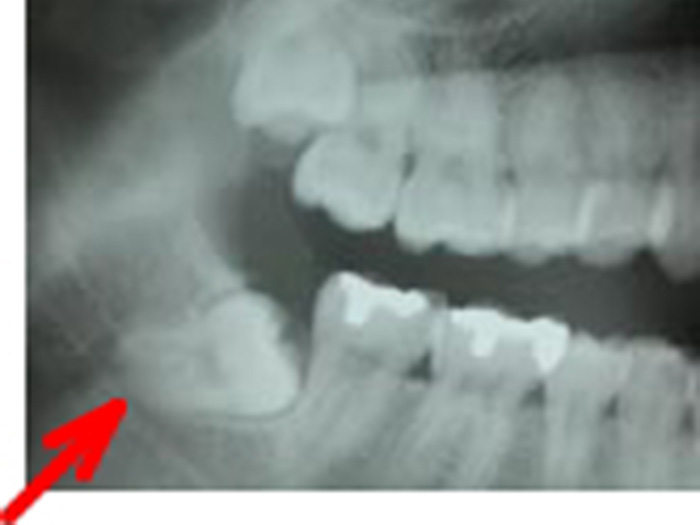

当科では、術前に歯科用3次元CTを用いて正確な診断を行い、炎症がある場合は抗生剤を用いて消炎後、抜歯を行っています。埋伏智歯の場合、歯肉粘膜の切開、骨の削除、智歯の分割、創部の縫合を必要とします。

右側下顎水平埋伏智歯

左側下顎水平埋伏智歯施術後